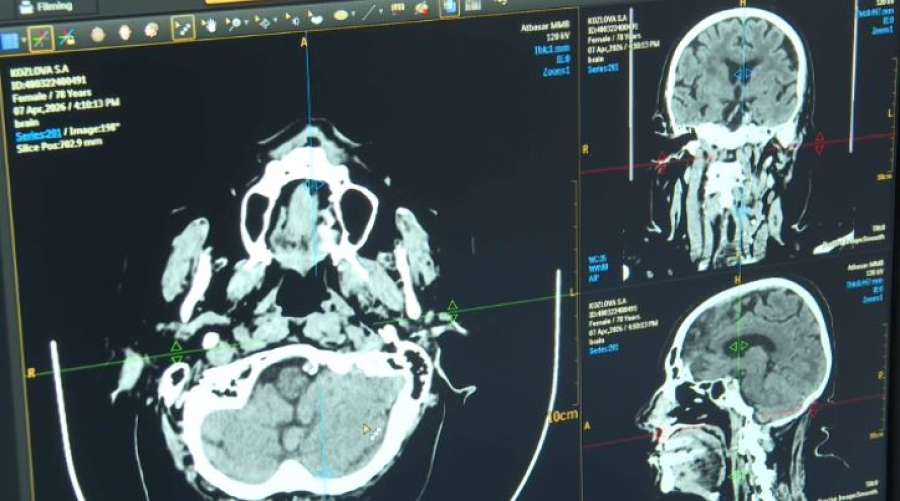

Врачи Акмолинской области используют искусственный интеллект для диагностики инсульта. Программа Cerebra AI анализирует КТ-снимки головного мозга и выявляет симптомы заболевания за считанные минуты. Новую технологию…